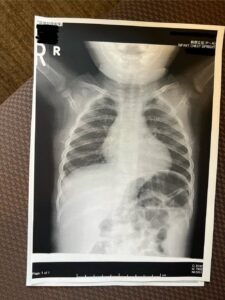

赤ちゃんや小さな子どもの体は、ぷくぷくと丸く柔らかくて癒されますね。あまりに可愛くて「中はどうなっているんだろう」と気になる人もいるかもしれません。@mi333221さんが、息子さんのレントゲン画像をThreadsに投稿すると「ほっこり」「キュンがマシマシ」などのコメントが寄せられ、話題になっています。

ある日、諸事情でレントゲン撮影することになった息子さん。出来上がった画像を見たママさんは、可愛すぎてひっくり返りました。レントゲン画像と実物を見比べることで、顔の外周に脂肪と思われる影が写っていたのです。

ママさんは「シルエットすらも可愛くて衝撃的でした」とレントゲンを見た感想を話してくれました。